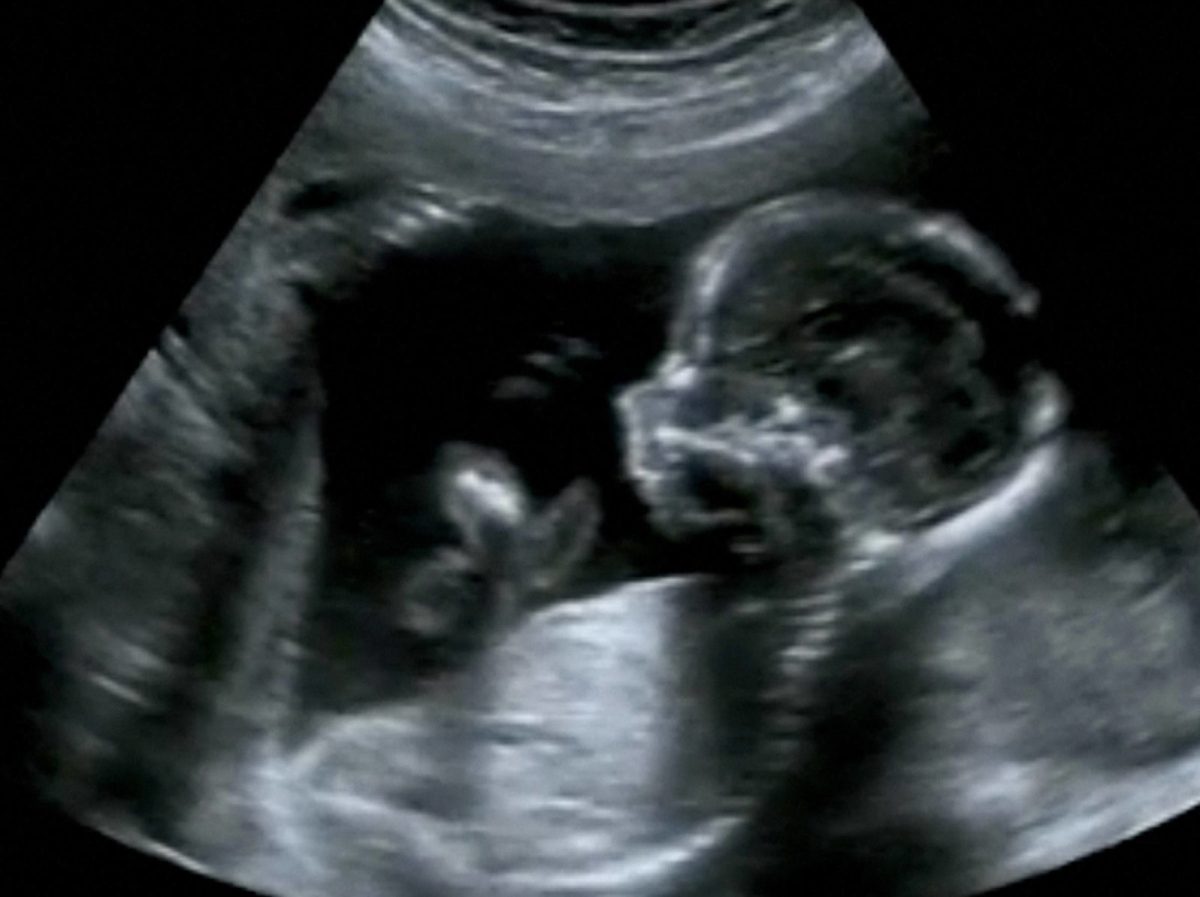

The decades long abortion legislation entitled Roe v Wade has been overturned via the Supreme Court in the United States.

The abortion issue has always been a contentious one both here in Northern Ireland and abroad which is set to continue following the recent Supreme Court ruling in the United States.